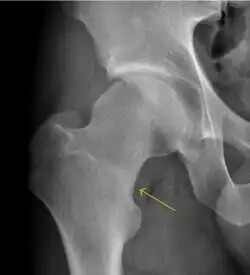

- Slipped capital femoral epiphyses (SCFE)

Slipped capital femoral epiphyses (SCFE) usually affect 11- to 14-year-old adolescents (Figure 4). Radiographs may show widening and irregularity of the physis and posterior inferior displacement of the capital femoral epiphysis. On the AP view Klein’s line, tangent to the lateral aspect of the femoral neck, does not intersect the femoral head indicating that it is displaced. SCFE may compromise the blood supply to the femoral head and cause avascular necrosis, mainly when there is instability between the fragments.[1]

-

Figure 4: (a) X-ray of a 10-year-old child with left hip pain. It was considered normal at emergency despite the widening of the left physis (arrow). Two weeks later epiphysiolysis was evident (b). Despite appropriate surgical reduction (c) osteonecrosis developed and femoral head collapsed 1 month later (d).[1]